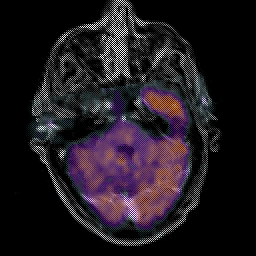

Glioma Overlay -- Slice #5

[Home][Help][Clinical] Slice 5